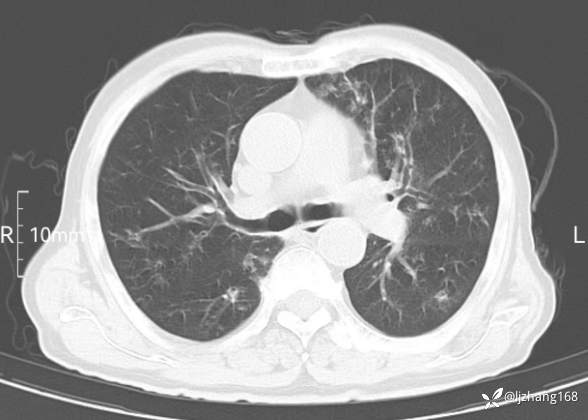

老年男患,咳嗽,气短,双肺多发间质性病变,何种感染?(有结果)

辅助检查:胸部CT:双肺肺气肿,间质性病变,血气分析:PH 7.413, PCO2 29.2mmHg, PO2,81.8mmHg,乳酸 3.3mmol/1,剩余碱-4.0mmol/1,HC03 18.8mmol/1。全血超敏C反应蛋白:超敏C反应蛋白 135.60 mg/L、 白细胞 14x19^9/L,中性粒细胞11.6x10^9/L。